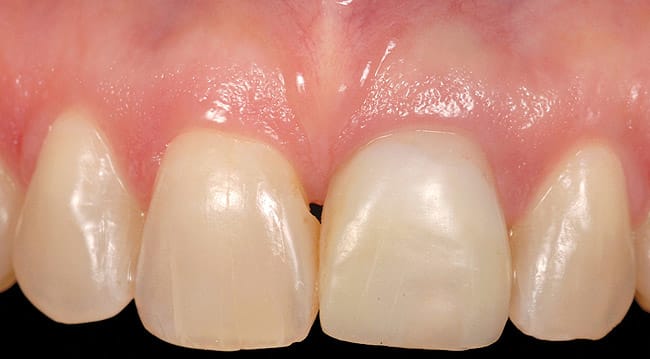

This patient presented with a non-restorable left central incisor due to external root resorption, as shown in the pre-treatment radiograph (Figure 1) and clinical photograph (Figure 2). The patient had good bone levels. The papilla positions were also good, but the cervical margins had some asymmetry with recession on the adjacent teeth. The goal was to preserve the papilla levels and the facial gingival margin level on the central incisors while also improving the gingival levels on the lateral incisors. Due to the patient’s cost concerns, the lateral incisors were not treated except for extending the CTG on the left central incisor only. A custom healing abutment was used to support the peri-cervical soft-tissue form.

The adjacent central incisor crown was to be replaced, which made it logical to do a cantilever provisional restoration as an interim provisional for the implant. The tooth was extracted in a flapless protocol. The implant was placed; in addition, a CTG was performed using a tunnel approach. Two weeks later, the soft-tissue volume was thick and well preserved. The final lithium-disilicate restorations were cut back and layered; they were opaque enough to mask the darkness of the endodontically treated right central incisor. The CTG resulted in preserving the cervical soft-tissue root prominence and also corrected the recession on the left lateral incisor. The all-ceramic restorations and zirconium abutments made the implant indistinguishable from the adjacent natural tooth (Figure 3).